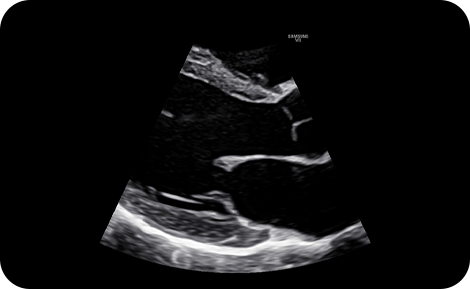

Reduce noise to improve

2D image quality

ClearVision enhances the edge contrast and creates sharp 2D images for optimal diagnostic performance.

precise imaging : ClearVision

2D PLAX zoom mode with ClearVision